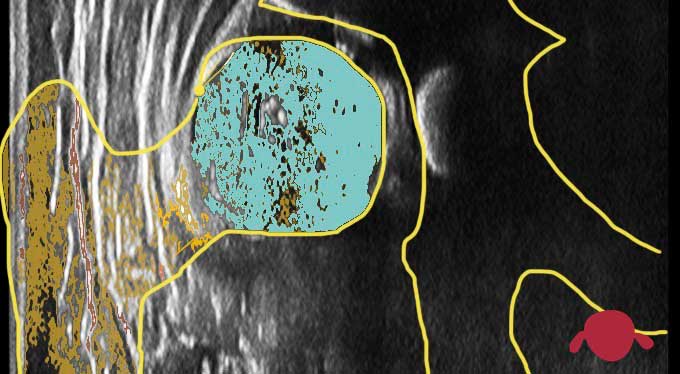

La ecografía busca una imagen “de frente” de la cadera. A eso los médicos le llamamos “corte coronal”. Es una imagen similar a ver la cadera en una radiografía “de frente”. Nos permite ver unas medidas para identificar si tenemos uno de los dos problemas de la cadera infantil (ver quién es quién en la cadera infantil).

Miraremos un ángulo que nos sirve para medir la profundidad del acetábulo, es decir, si el cuenco es muy cuenco o más bien plato hondo o incluso plato llano.

Nos gusta que mida al menos 60º ese ángulo “alpha” que mide la profundidad del acetábulo. Es un límite arbitrario, igual que ir a 121 km/h no es correcto pero ir a 120 km/h sí lo es (aunque no haya una clara diferencia de seguridad entre ir a 120 vs 121). Además, a la hora de trazar las líneas que definen ese ángulo alpha de profundidad del acetábulo entra el error humano. Un mismo médico tiene un margen de error de unos 2º a la hora de pintar esas líneas. De este modo 58º (escaso) podrían ser 60º (correcto) según quién lo mida. Por eso nunca nos vas a ver preocupados si vemos un resultado ligeramente inferior a 60º. Simplemente esperaremos un poco más de tiempo y volveremos a repetir la ecografía. Seguro que en la siguiente ecografía mejora y se acerca más a los 60º sin realizar ninguna intervención (sin poner aparatos a las caderas)

La otra medida que hacemos en la ecografía es cuánta cabeza femoral (la bola) está dentro del acetábulo (el cuenco). A esto lo llamamos cobertura. Nos gusta que sea del 50%, es decir, que la mitad de la bola esté dentro del cuenco y la mitad fuera. No nos gusta esta medida si es menor de 40% ya que si la bola no está bien dentro del cuenco, éste no se va a desarrollar bien. Medidas de cobertura muy bajas significan que la bola no está dentro del cuenco. A eso le llamamos subluxación o incluso luxación cuando toda la bola está fuera del cuenco.